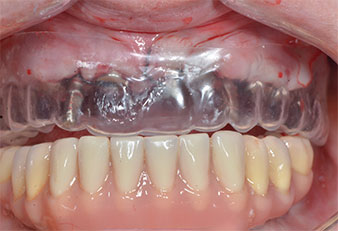

Drei Jahre später war es Zeit für eine gleichartige Oberkieferprothese. Basierend auf der DVT-Planung wurde durch Verwendung kurzer Implantate eine Sinusaugmentation vermieden und die geplanten Implantatpositionen wurden mit einer Bohrschablone auf den Kieferkamm übertragen (Abb. 1 und 2).

Abb. 1: Präoperative Ansicht des Kieferkamms, die Implantatpositionen wurden mithilfe einer Kunststoff-Bohrschablone markiert. Wegen des niedrigen Kieferkamms sind im Seitenzahnbereich sehr kurze Implantate geplant.

Kunststoffschablone

Abb. 9: Eine Kunststoffschablone zeigt, dass die Platzverhältnisse ausreichen, um die vorhandene Prothese als Provisorium auf den temporären Implantaten zu verwenden.